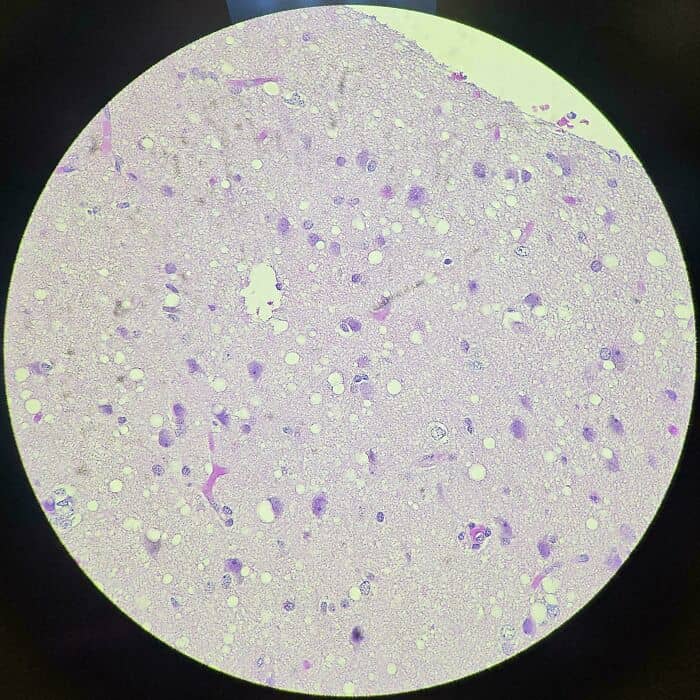

#65 Brain Tissue Of A Cjd Patient Under A Microscope, Showing Holes Everywhere (White Circles). Cjd Is Closely Related To “Zombie Deer Disease” (Cwd). It Is 100% Fatal And There Is No Treatment